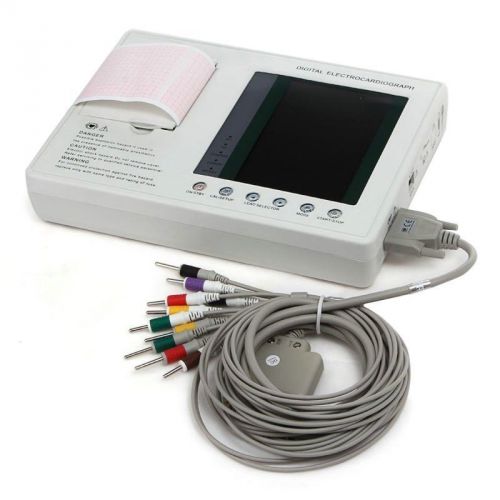

HOT Sale!!12 Lead 7inch Color LCD 3-channel ECG/EKG Machine with interpretation

2015 HOT 3-Channels Color LCD ECG Holter ECG/EKG Holter Monitor System

Hot USA FDA Handheld 24h 12-leads Dynamic ECG System with PC software,12 channel